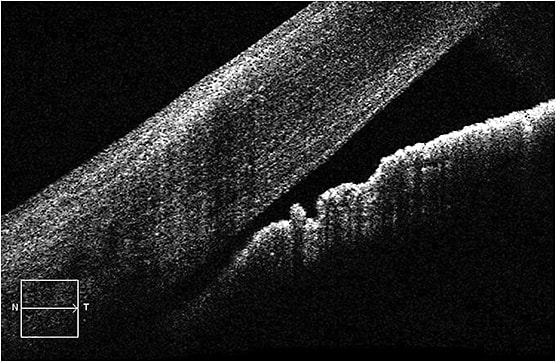

SCANNING TOMOGRAPHY

SD-OCT, OCT-A and OCT fall under here. To start, SD-OCT provides measurements of the thickness of the neuroretinal tissue that is characteristically damaged in glaucoma; the RNFL, the GCC and the neuroretinal rim. Specifically, various OCT platforms present neuroretinal tissue thickness data in comparison to their respective reference databases of healthy patients, displaying the tissue as normal, borderline or outside normal limits.

OCT-A employs motion contrast (comparison of sequential B scans of the same static retinal or ONH area) to detect the movement of red blood cells. This allows for a non-invasive, quantitative assessment of the vascular health.

Clinical pearl: Optometrists should look to OCT-A as a means of demonstrating the reduced density of vasculature at the optic nerve in the circumpapillary retina and maculas of patients who have early glaucoma.

OCT enables the early diagnosis of glaucoma. In fact, a study in Ophthalmology shows glaucomatous RNFL were detected up to eight years prior to detection of damage with standard perimetry.

Clinical pearl: O.D.s should be aware that thin tissue is likely indicative of worse disease, and thick tissue is more likely indicative of good tissue health. Additionally, to first confirm that the tissue thinning is consistent with glaucoma, O.D.s should analyze the macular and ONH data together. After all, failure to look at all tissues that can be affected can result in failure to accurately diagnose the extent of glaucomatous damage. (For additional information on this technology, see https://bit.ly/38ABFtc .)